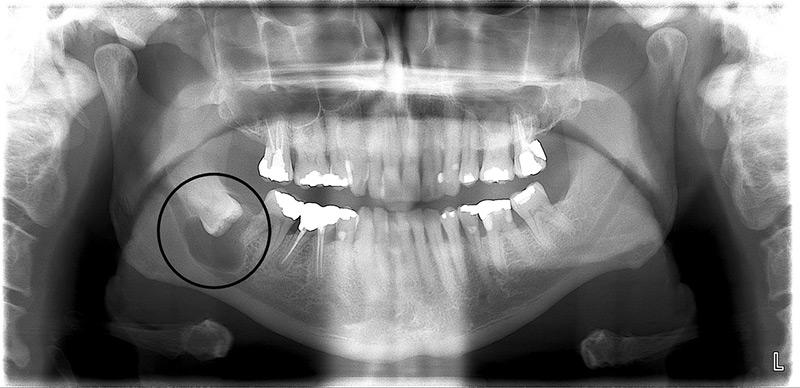

How can I tell if my wisdom tooth is impacted?

Is an X-ray necessary before wisdom tooth extraction?